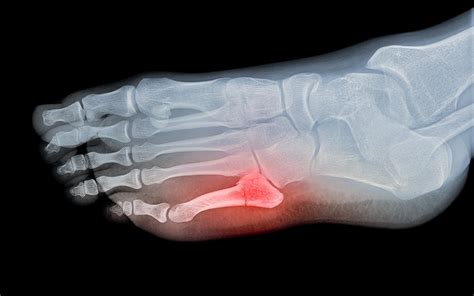

A fractured foot is a common orthopedic injury that can range from a tiny hairline crack in one of the many small bones to a complex break involving multiple bones. Whether you have suffered a stress fracture from overuse or an acute break from a sudden impact, understanding the nature of your injury is the first step toward effective recovery. Because the foot is a complex structure consisting of 26 bones, 33 joints, and over 100 muscles, tendons, and ligaments, it is essential to seek professional medical advice to ensure proper healing and avoid long-term complications.

When you visit a medical professional for a suspected top fractured foot, they will perform a physical examination to check for localized tenderness and swelling. To confirm the diagnosis and determine the extent of the damage, they will utilize various imaging techniques:

• X-rays: The primary tool used to visualize the bone and determine if a crack or break exists.